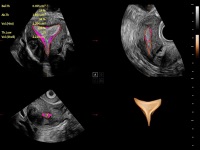

盆底自動(dòng)測(cè)量(2D)

盆底自動(dòng)測(cè)量(3D)